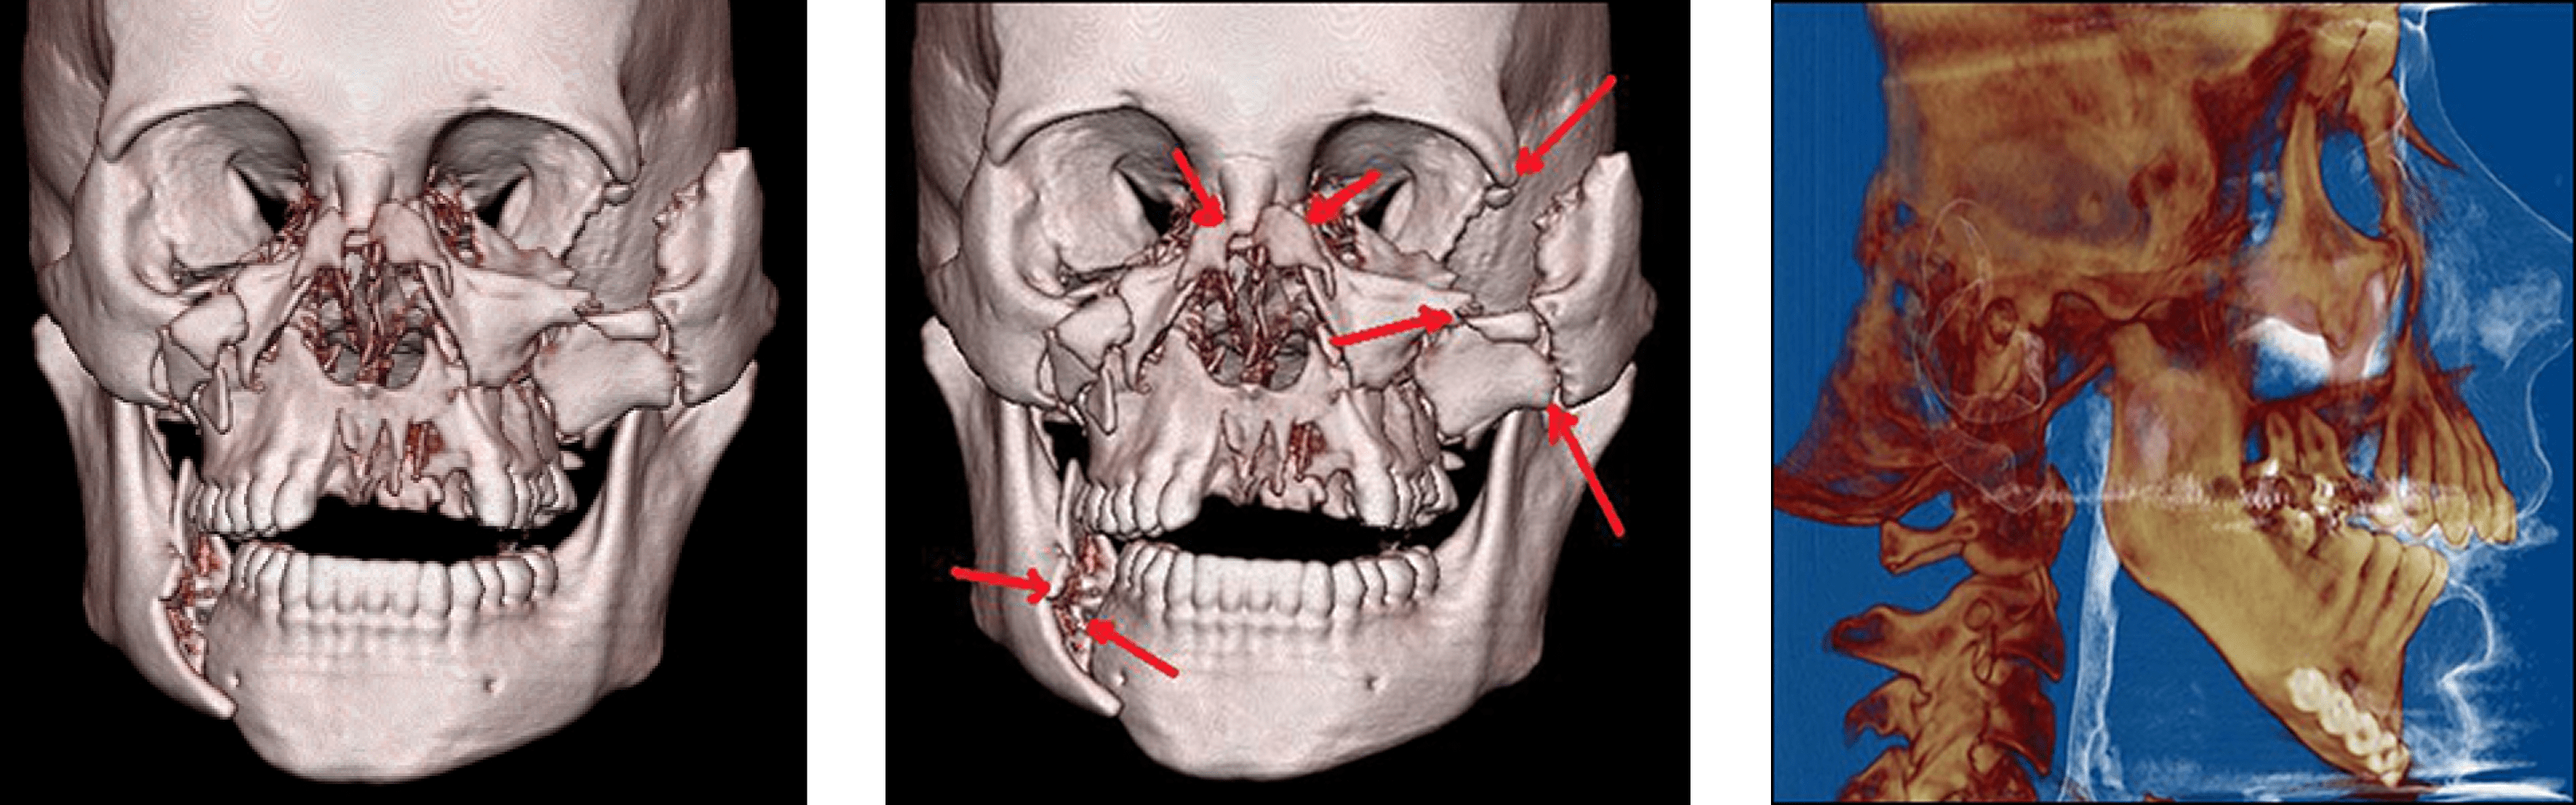

Facial Fractures

There are a number of possible causes of facial trauma such as motor vehicle accidents, accidental falls, sports injuries, interpersonal violence, and work-related injuries. Types of facial injuries can range from injuries of teeth to extremely severe injuries of the skin and bones of the face (cheek, nose, orbit, upper and lower jaw). Injuries to the face, by their very nature, impart a high degree of emotional, as well as physical trauma to patients. The science and art of treating these injuries requires special training involving a “hands on” experience and an understanding of how the treatment provided will influence the patient’s long term function and appearance.

Injuries of the facial bones

Fractures of the bones of the face are treated in a manner similar to the fractures in other parts of the body. The specific form of treatment is determined by various factors, which include the location of the fracture, the severity of the fracture, the age, and general health of the patient. When an arm or a leg is fractured, a cast is often applied to stabilize the bone to allow for proper healing. Since a cast cannot be placed on the face, other means have been developed to stabilize facial fractures. One of these options involves wiring the jaws together for certain fractures of the upper and/or lower jaw.

Certain other types of fractures of the upper and lower jaws, cheek bone and frontal bone are best treated and stabilized by the surgical placement of small plates and screws at the involved site. This technique is called “rigid fixation” of a fracture. The relatively recent development and use of rigid fixation has profoundly improved the recovery period for many patients, allowing them to return to normal function more quickly. The incisions are designed to be small, placed intraorally and if it is necessary to go through the skin they are hidden to avoid visible scars.

Fractures of the nose are treated with reduction and stabilization with intranasal packing (2-3 days) and external splint (7-10 days). Fractures of multiple bones of the face are called panfacial fractures, the repair of these fractures is more difficult and several hours of surgery are needed to obtain a good result. In some cases additional procedures have to be done to reconstruct the facial structures.